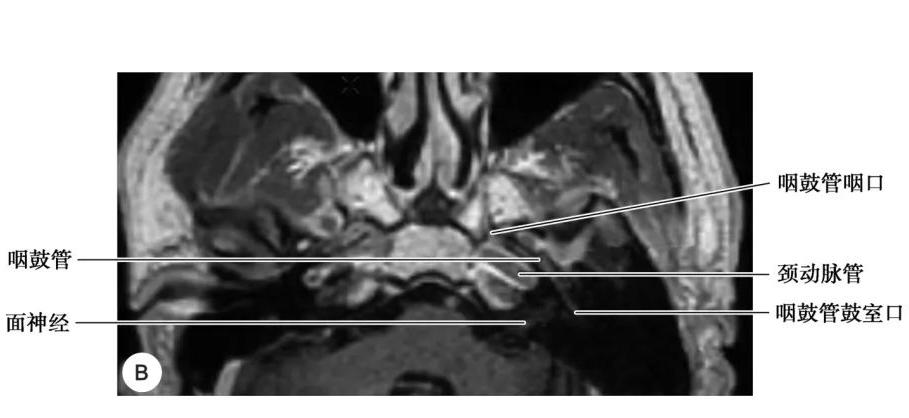

咽鼓管结构

A. CT;B. MRI

2.咽鼓管

咽鼓管为连接鼻咽腔与鼓室的通道,向内通鼻咽腔,开口于咽鼓管咽口,向外通鼓室前壁,开口于咽鼓管鼓口,鼻咽癌可经咽鼓管侵入中耳。